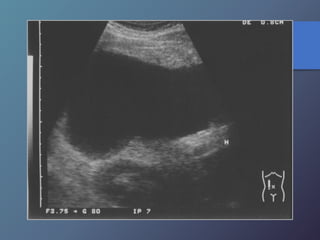

Traumatismo Hepático

• La lesión hepática es a predominio del lóbulo derecho.

• Mayor particularidad en segmento posterior.

• Mayor frecuencia por laceración peri vascular.

• Se producen hematomas subcapsulares,

pericapsulares o aislados.

• La hemorragia en las primeras 24 horas es ecogénica y

posteriormente se hace mas hipoecogénica.

• Entre las dos o tres semanas se puede observar gran

cantidad tejido de granulación.

Hígado post- trauma

Hematoma sub capsular hepático